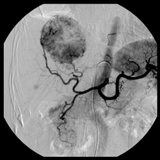

この装置では、脳神経外科が頸部より上の動脈や静脈の撮影と治療、消化器内科が肝臓がんの撮影と治療、移植外科が透析患者様のシャントの撮影と治療を行っています。ひとつの写真に収まる範囲がとても広いため、特に頭部や腹部を撮影することに適している装置です。また、血管を立体的に表示する3D画像の撮影も行うことが出来ます。